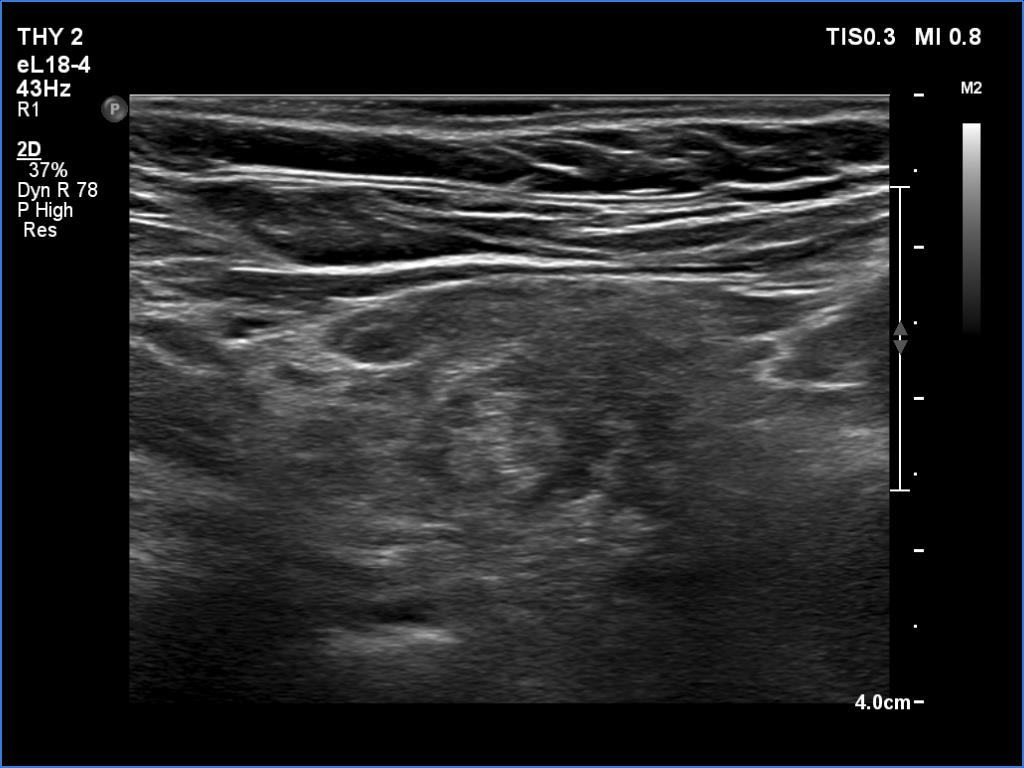

Ultrasonography: The right lobe had several discrete hypoechoic areas within an echonormal background. The left lobe had a larger hypoechoic area resembling the presentation of central hypoechoic area-type form.

Comment: The central hypoechoic area-type presentation is always bilateral. The pattern in this case should be regarded as focal form of lymphocytic thyroiditis.